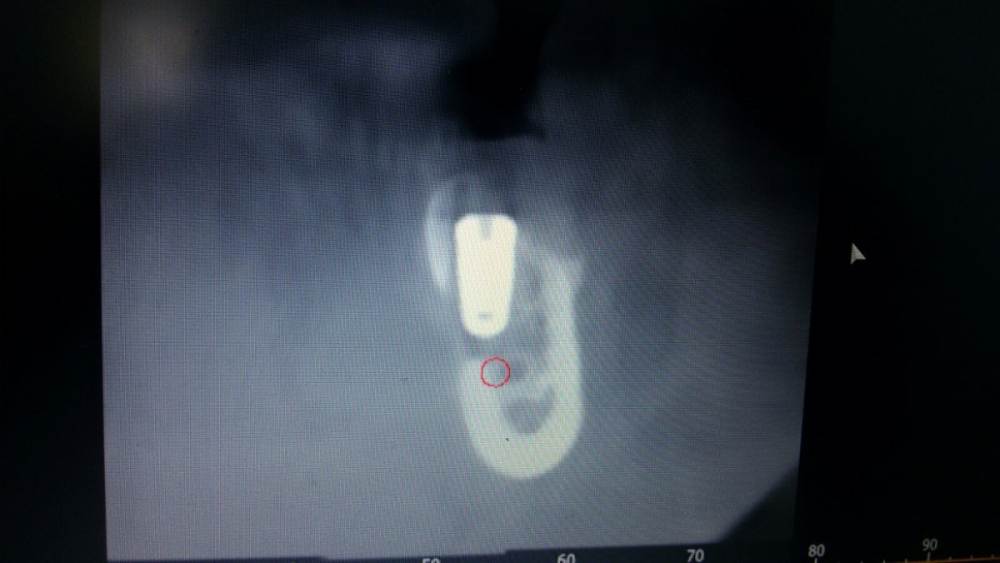

chealena Опубликовано 14 августа, 2021 Поделиться Опубликовано 14 августа, 2021 Здравствуйте ! В среду мне установили 4 импланта по две на каждые стороны нижние, слева также удаляли зуб и туда сразу ставили имплант. После этого у меня сейчас онемевшая губа и часть зубов и часть подбородка, что мне делать? Врач говорит что все нормально и нерв не был задет, а я вижу что на кт снимке идёт траншея до нерва , как будто он просверлил туда. Говорит мне ничего не делать и просто ждать. Но онемение не проходит, уже и отёк спал , а онемение есть и это ужасно противно, и когда пальцем вожу по этому месту очень неприятно как будто песок. Зуб слева первый имплант на снимке. Подскажите пожалуйста что делать! Ссылка на комментарий

Irouil Опубликовано 14 августа, 2021 Поделиться Опубликовано 14 августа, 2021 Как и что могло случится - это спрашивать стоит только у того человека, который видел своими глазами что и как случалось. Иначе говоря, эти вопросы надо задавать лечащему врачу. Выкручивание имплантов, судя по предоставленным снимкам, никак не повлияет на ситуацию с онемением. Но это не отменяет Вашей симптоматики, а значит какое-то влияние на нерв есть. Неврологическая терапия поможет снизить это влияние и ускорить процесс восстановления чувствительности. Ссылка на комментарий

Irouil Опубликовано 16 августа, 2021 Поделиться Опубликовано 16 августа, 2021 15.08.2021 в 00:45, chealena сказал: Но если нерв не поврежден почему у меня пол губы немые вместе с подбородком и частью зубов? Воздействия на нерв не ограничиваются только его повреждениями. Даже отёк от проведённой операции способен создать иногда достаточную компрессию чтобы вызвать транзиторную парестезию. Импланты в канал не пенетрируют, это самое главное. Руками хирурга тут особо нечего изменить/исправить. Применение физиотерапевтических процедур может ускорить реабилитацию. 2 Ссылка на комментарий